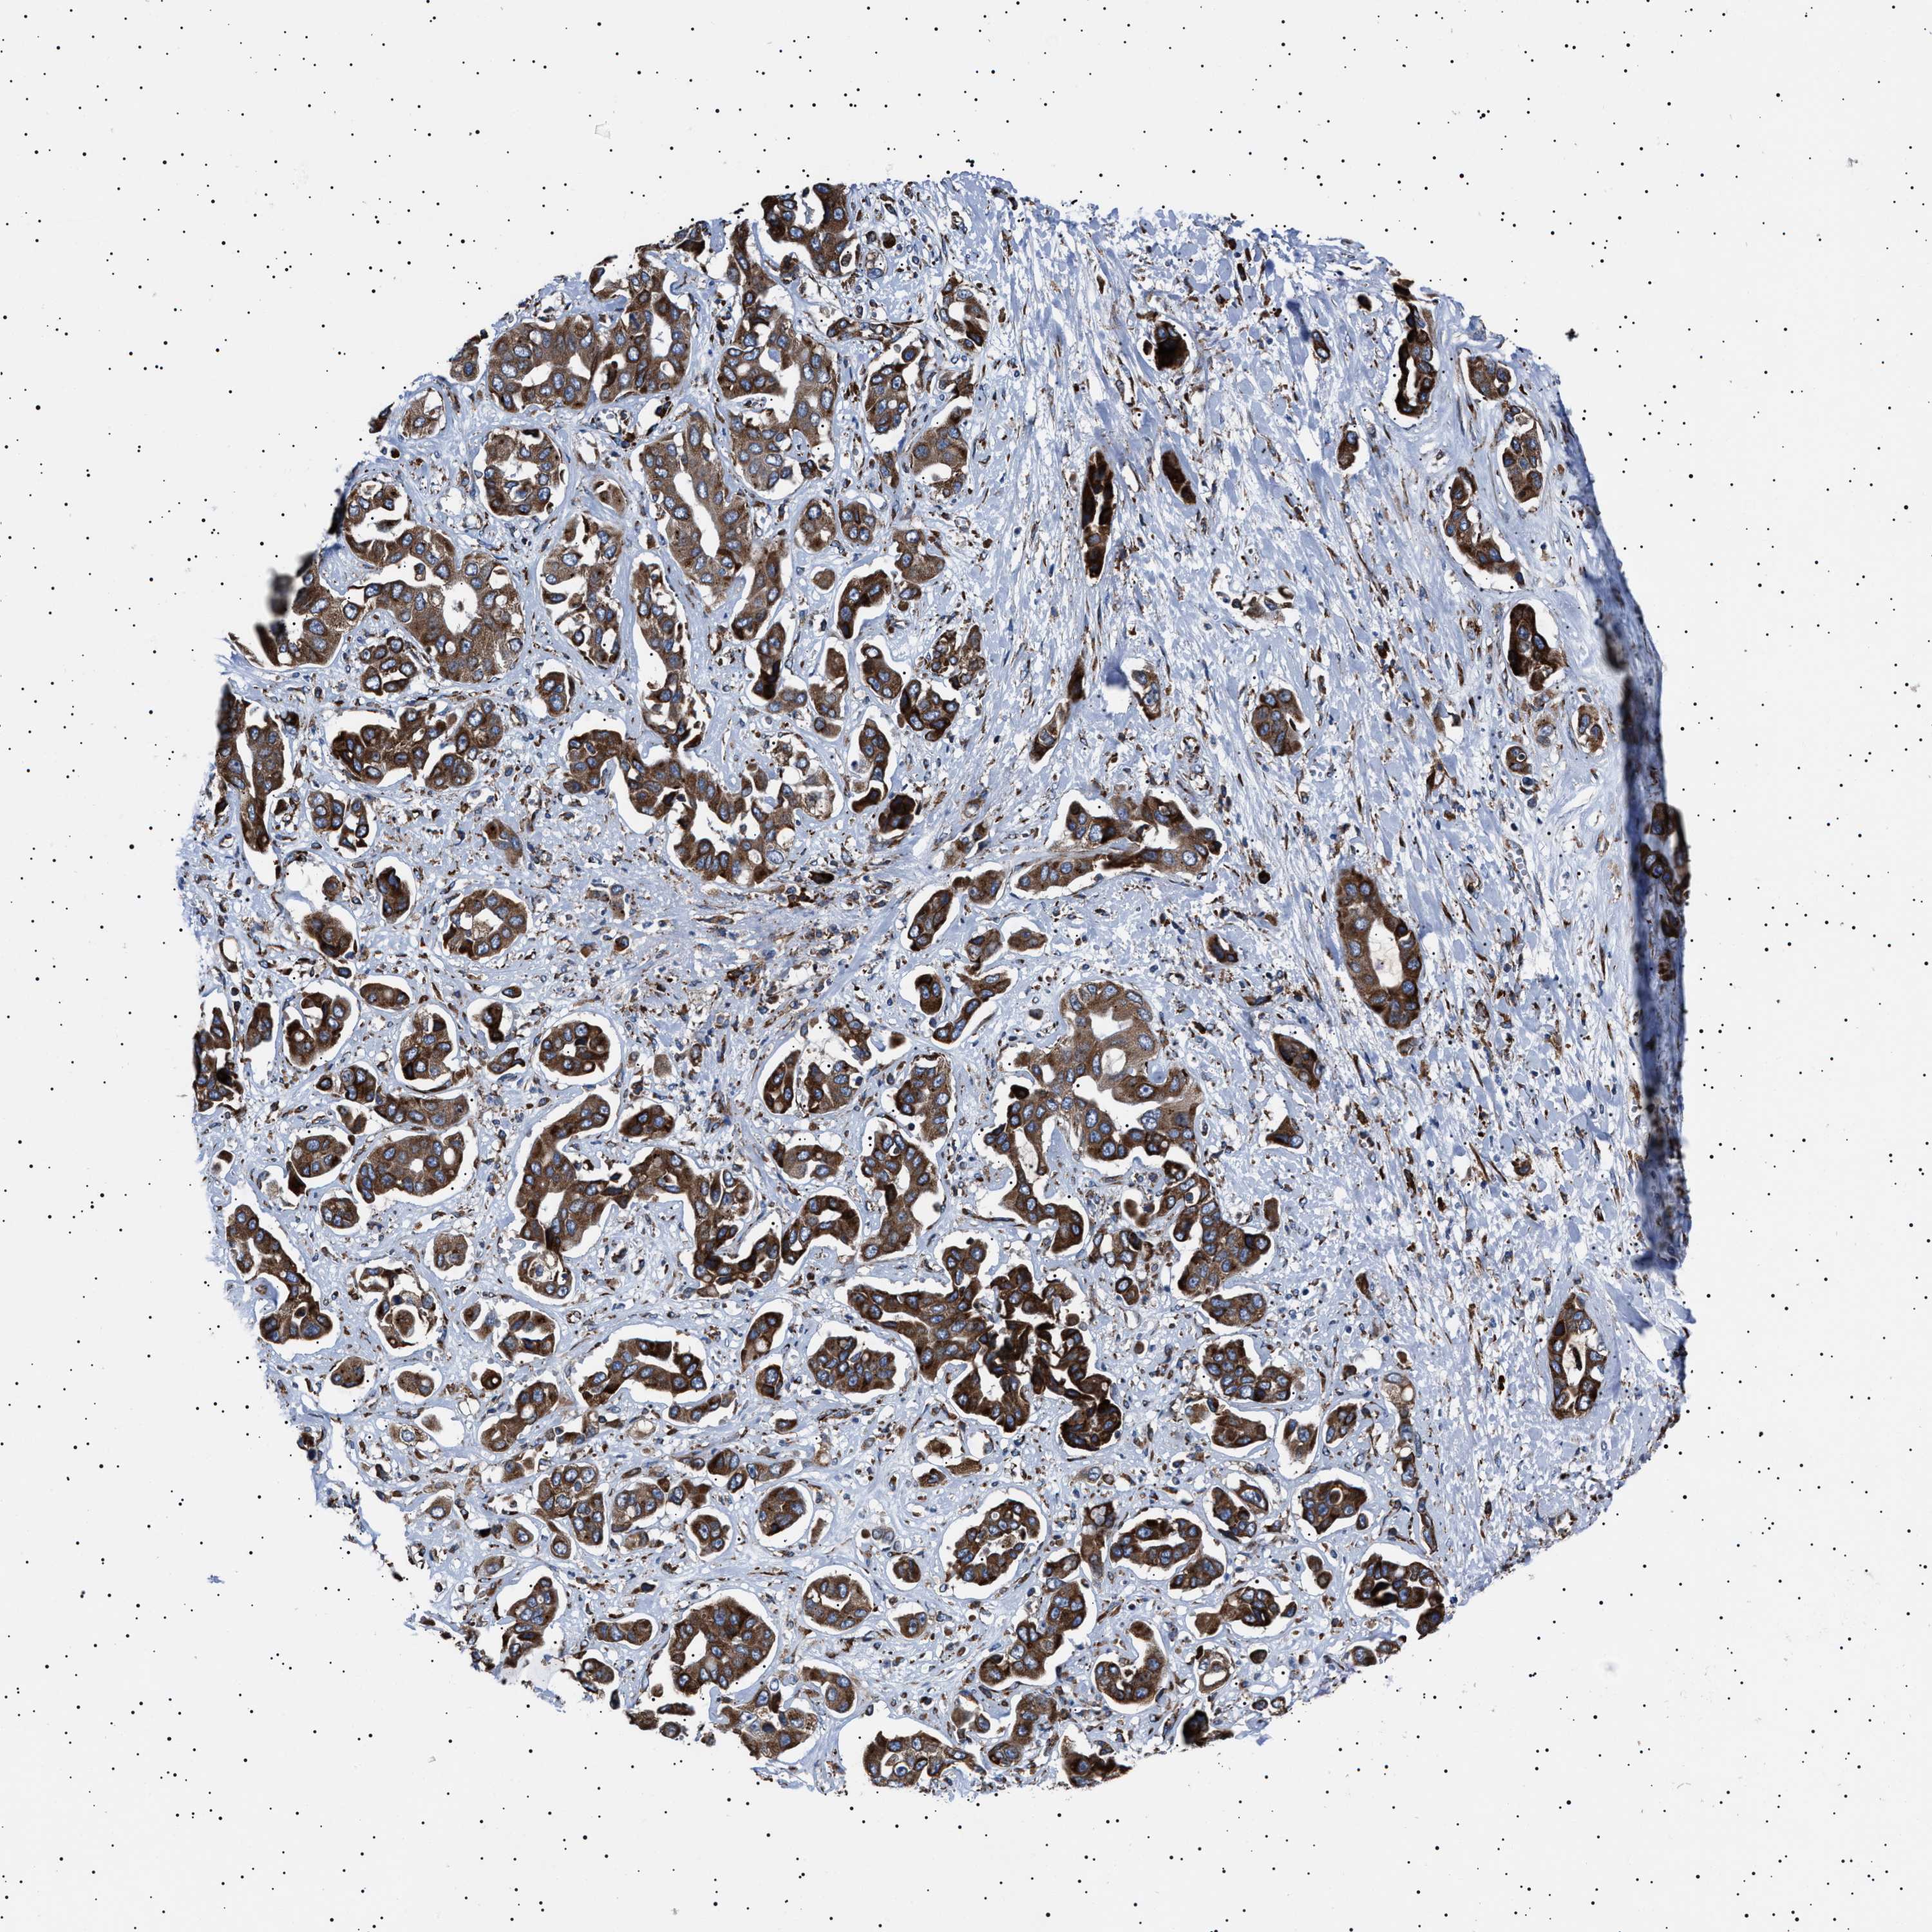

LIVER CANCER - Protein expressioni

A mouse-over function shows sample information and annotation data. Click on an image to view it in a full screen mode. Samples can be filtered based on level of antibody staining by selecting one or several of the following categories: high, medium, low and not detected. The assay and annotation is described here.

Note that samples used for immunohistochemistry by the Human Protein Atlas do not correspond to samples in the TCGA dataset.

Antibody stainingi

Antibody staining in the annotated cell types in the current human tissue is reported as not detected, low, medium, or high, based on conventional immunohistochemistry profiling in selected tissues. This score is based on the combination of the staining intensity and fraction of stained cells.

Each image is clickable and will lead to virtual microscopy that enables deeper exploration of all samples and also displays staining intensity scores, fraction scores and subcellular localization as well as patient and tissue information for each sample.

Antibody HPA001915

Antibody HPA021542

Staining

High

Medium

Low

Not detected

Intensity

Strong

Moderate

Weak

Negative

Quantity

>75%

75%-25%

<25%

None

Location

Nuclear

Cytoplasmic/membranous

Cytoplasmic/membranous,nuclear

Cholangiocarcinoma

Carcinoma, Hepatocellular, NOS